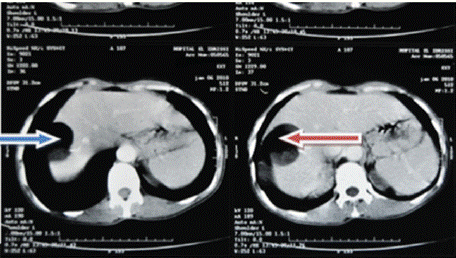

Ultrasound of the right liver (anterior sector) revealed a heterogeneous cystic image with a thin wall, suggestive of a type IV hydatid cyst. Abdominal CT confirmed a multiloculated cystic lesion containing fatty, calcified, and fluid components, suggestive of a hepatic teratoma. An MRI scan further supported the diagnosis, showing a grossly oval lesion in the hepatic dome measuring 57 × 48 mm. The lesion contained a fluid level with a supernatant displaying T1 hypersignal, T2 hyposignal, and a dependent portion in T1 and T2 isosignal, without enhancement after gadolinium injection — findings suggestive of a modified hydatid cyst.

Figure 4: Red arrow: well-defined rounded lesion in segment VIII with

probable cystic NHA image.